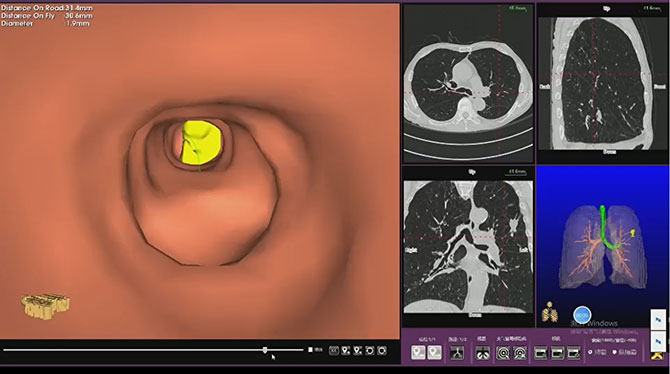

精准导航。术前通过虚拟支气管导航规划路径,术中结合细支气管镜推进与移动CT实时引导,确保1.9mm冷冻消融针精准抵达肿瘤内部。

术前根据CT路径规划